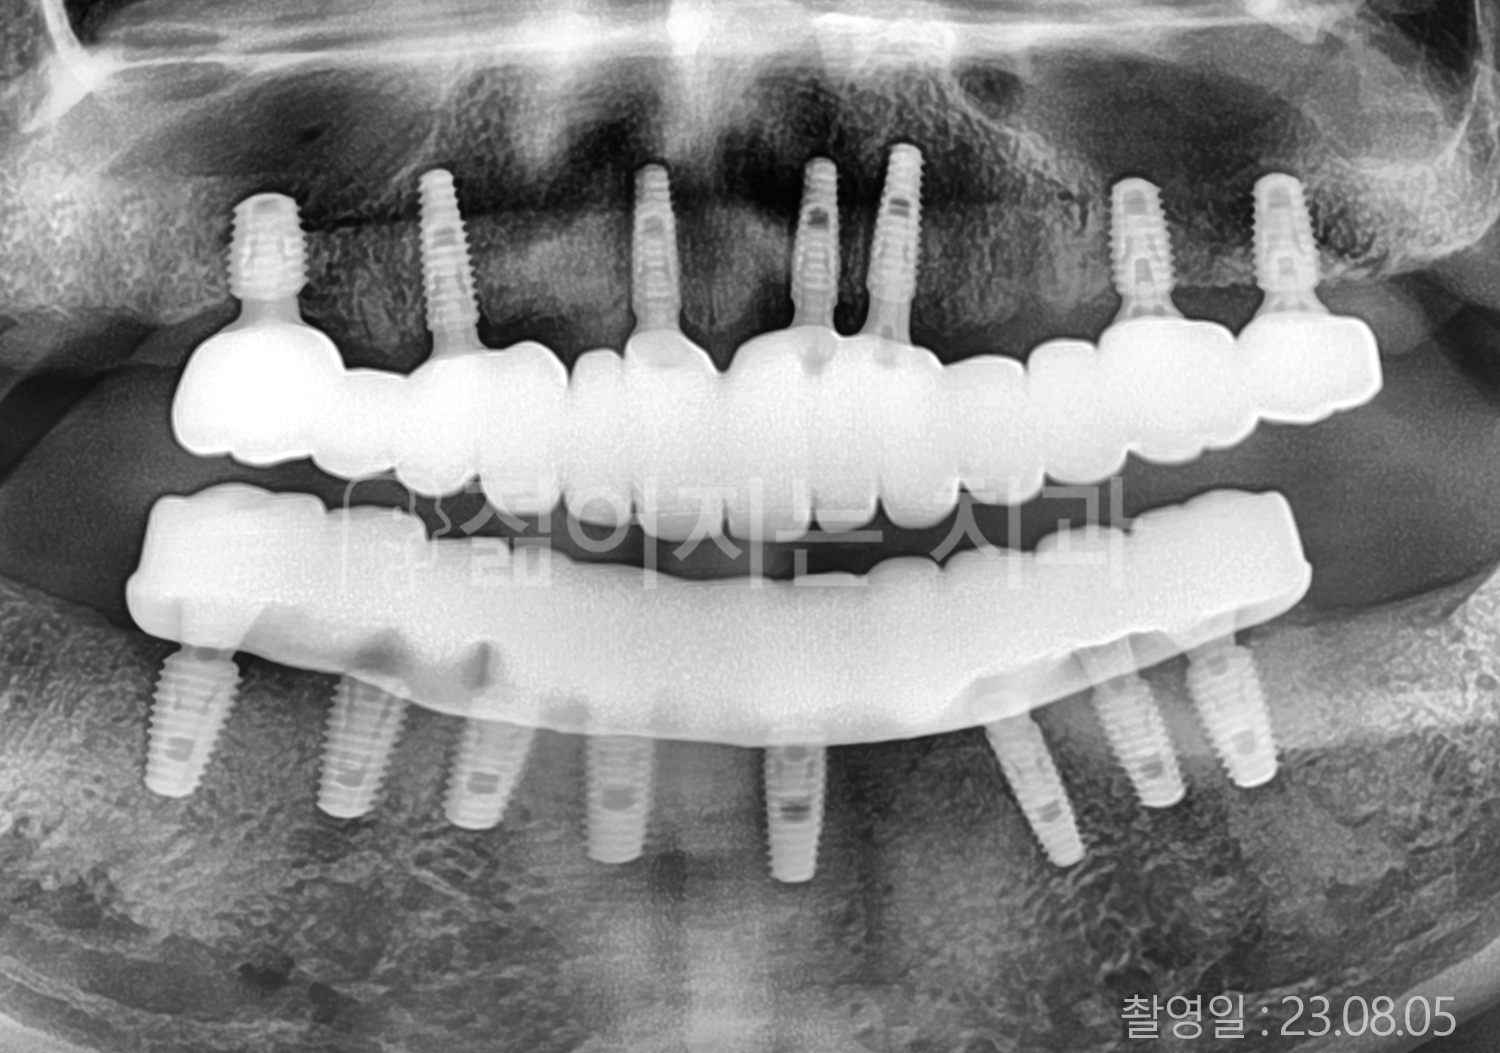

• 60대 전체치아 10개 이상 임플란트